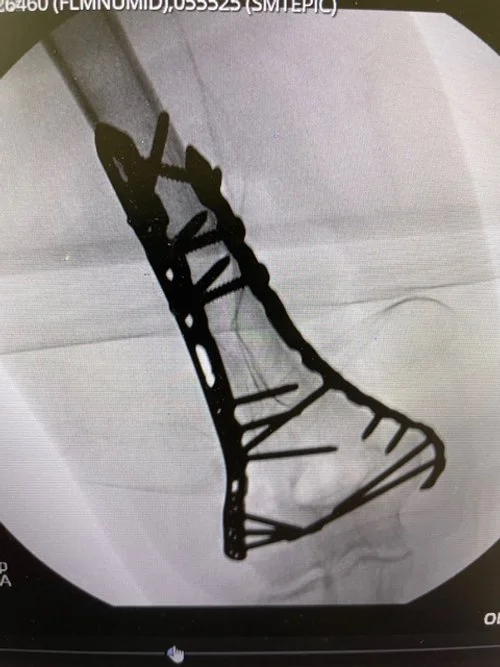

Medical imaging showing a metal surgical implant, likely a fixation device, attached to a bone during a medical procedure.